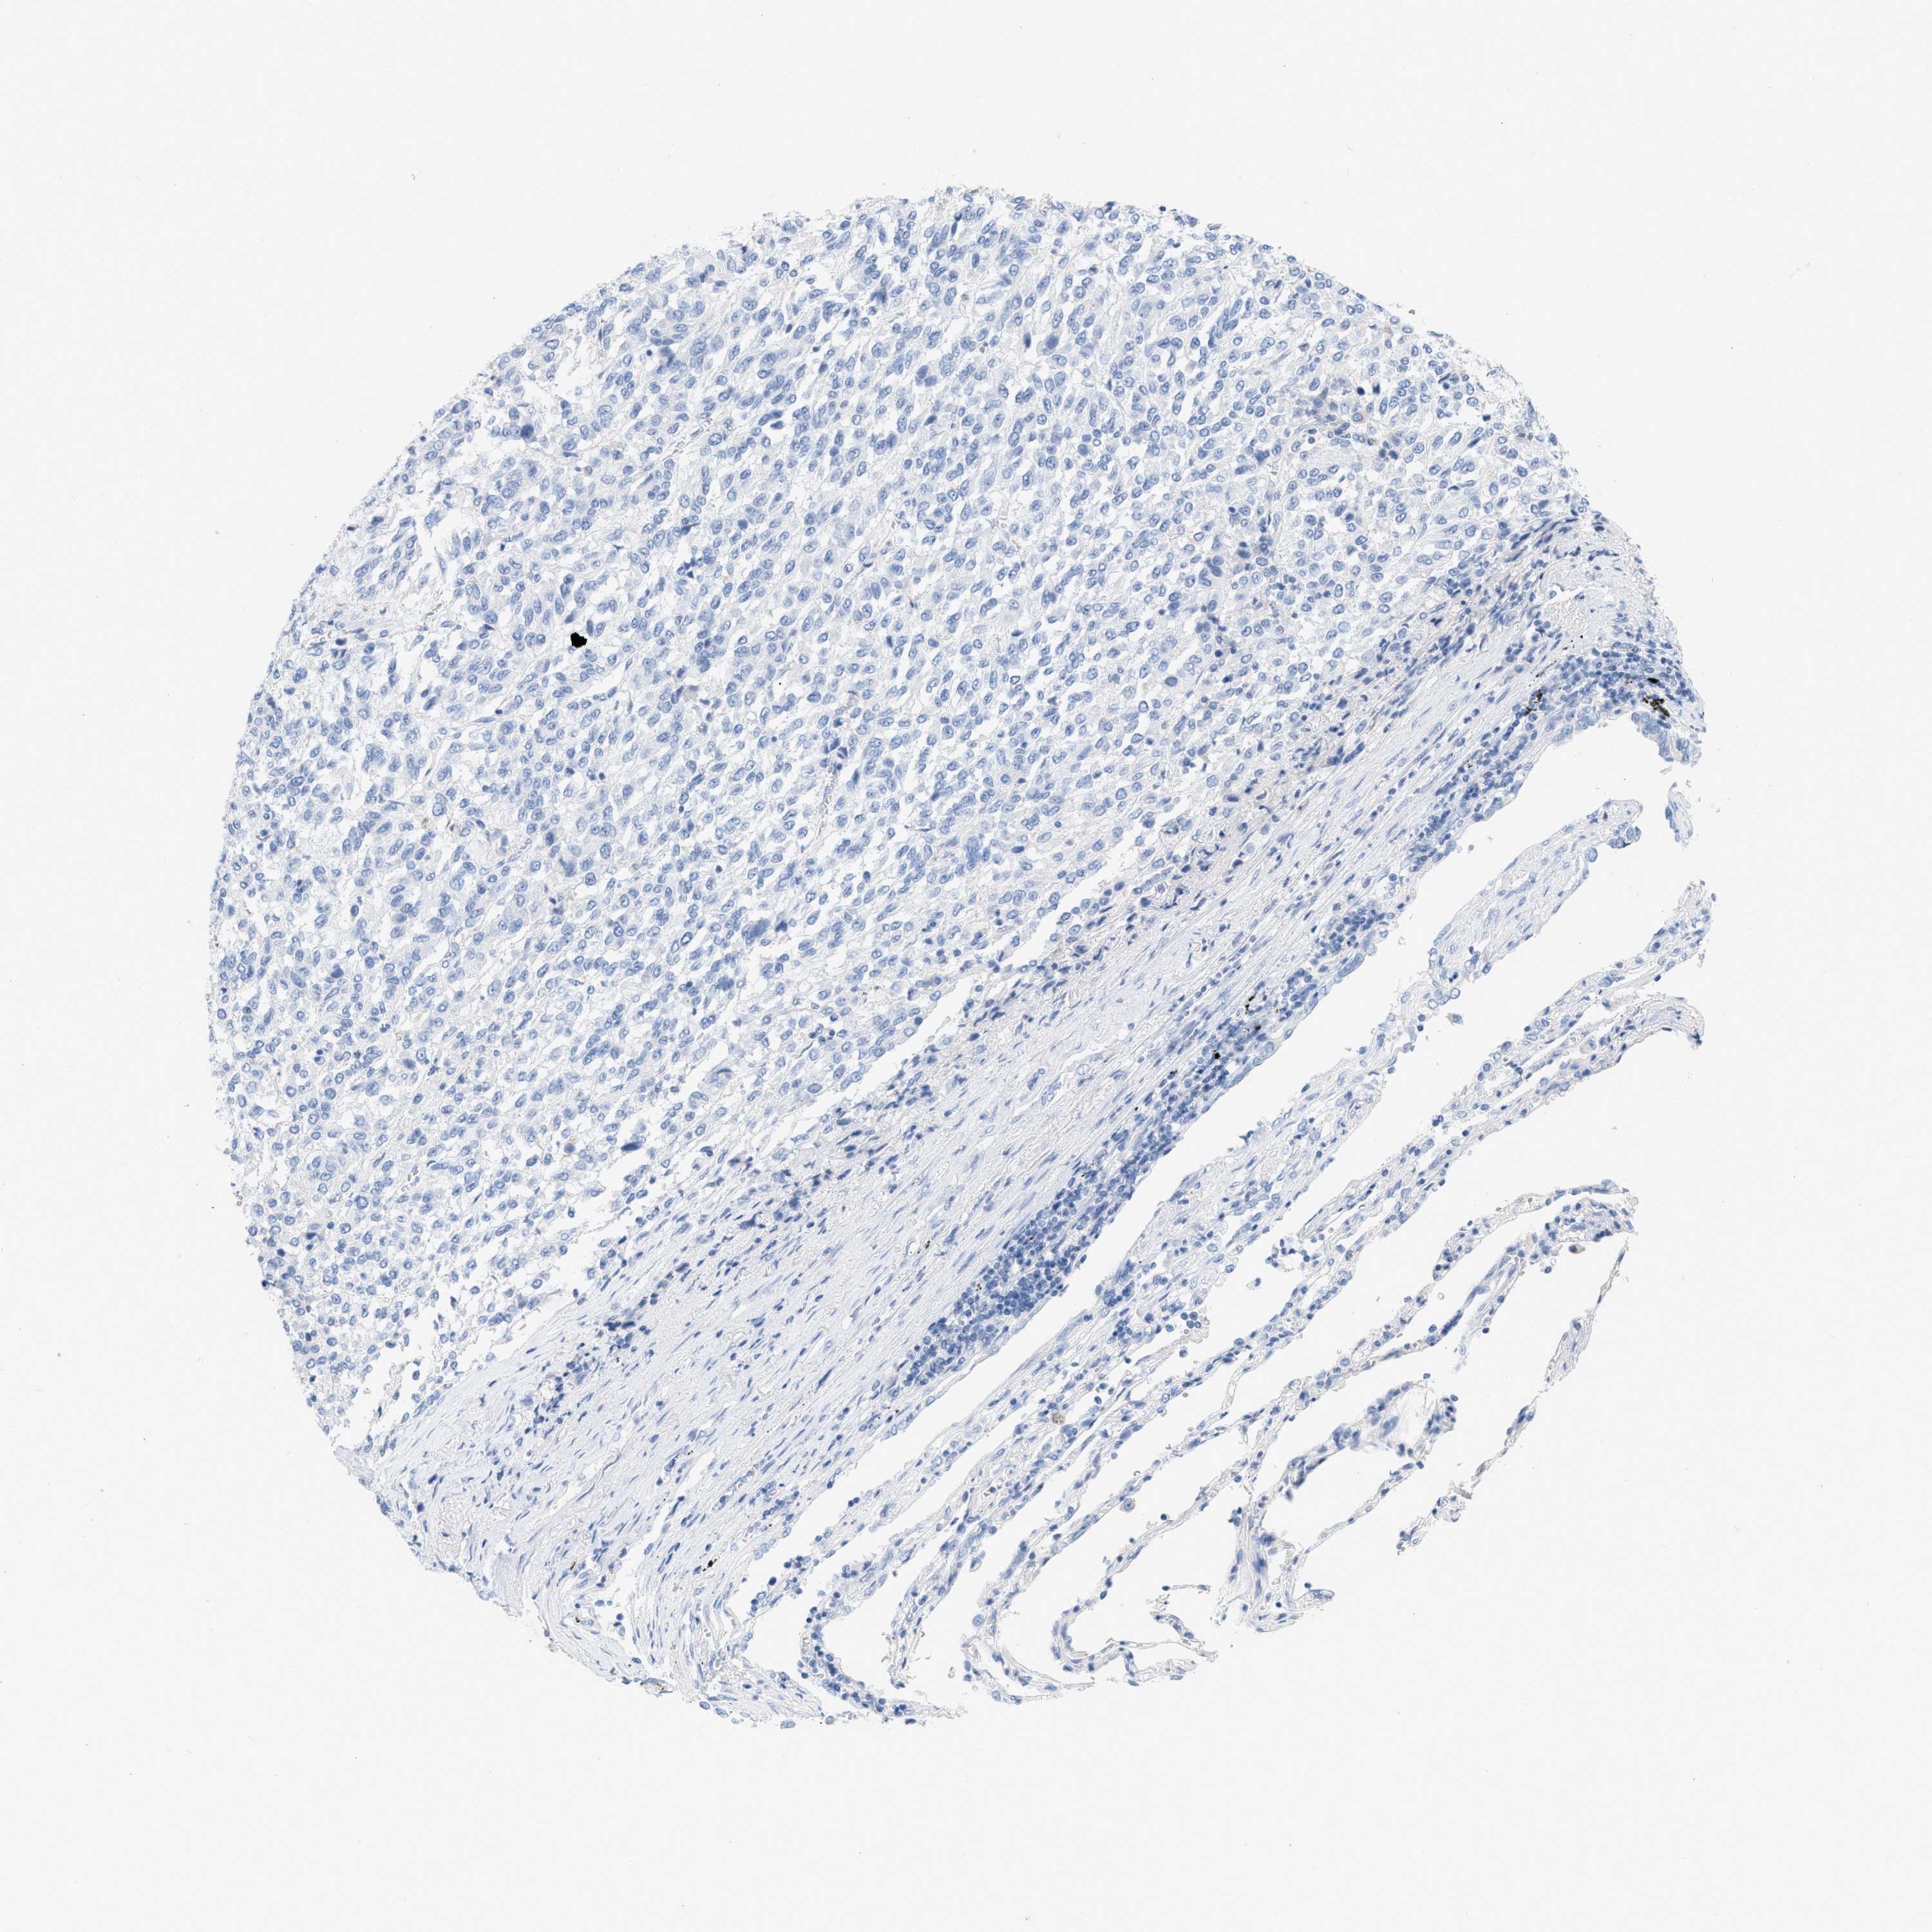

MELANOMA - Protein expressioni

A mouse-over function shows sample information and annotation data. Click on an image to view it in a full screen mode. Samples can be filtered based on level of antibody staining by selecting one or several of the following categories: high, medium, low and not detected. The assay and annotation is described here.

Note that samples used for immunohistochemistry by the Human Protein Atlas do not correspond to samples in the TCGA dataset.

Antibody stainingi

Antibody staining in the annotated cell types in the current human tissue is reported as not detected, low, medium, or high, based on conventional immunohistochemistry profiling in selected tissues. This score is based on the combination of the staining intensity and fraction of stained cells.

Each image is clickable and will lead to virtual microscopy that enables deeper exploration of all samples and also displays staining intensity scores, fraction scores and subcellular localization as well as patient and tissue information for each sample.

Antibody HPA001667

Antibody CAB016724

Malignant melanoma, NOS

Malignant melanoma, Metastatic site